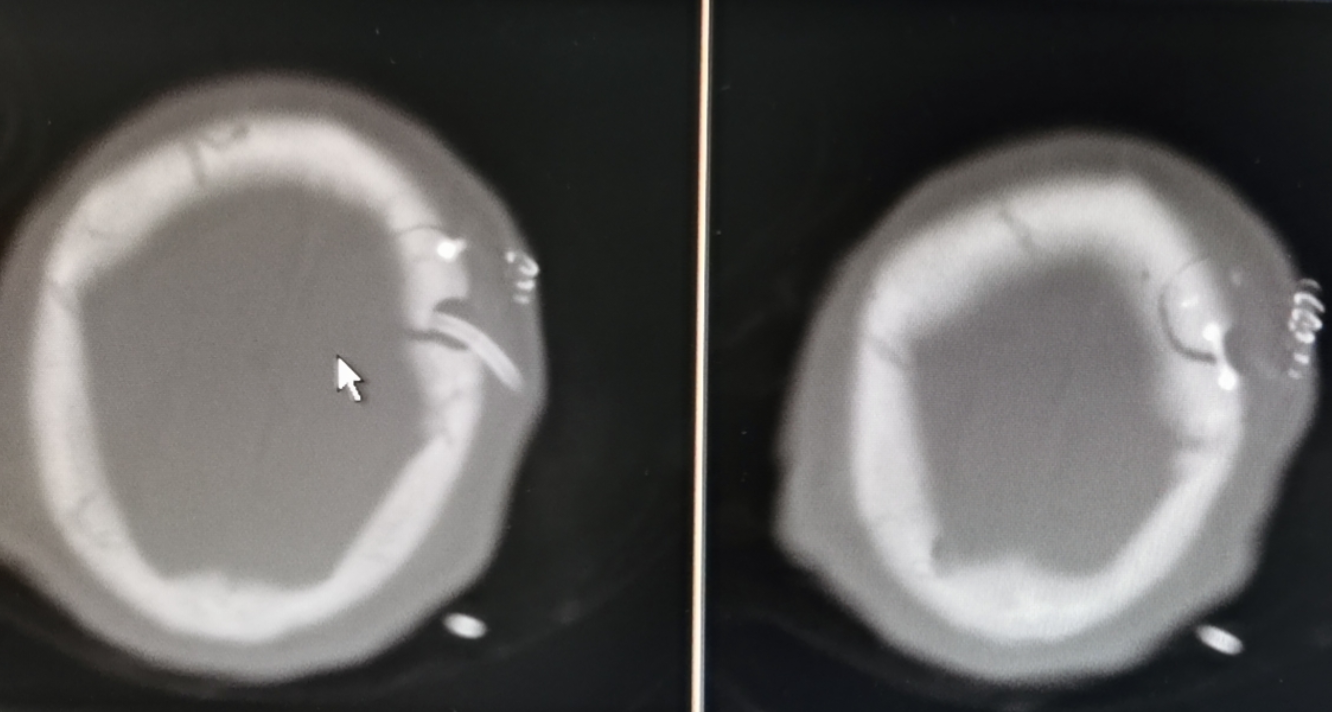

术后CT提示小骨窗

神经内镜微创治疗高血压脑出血